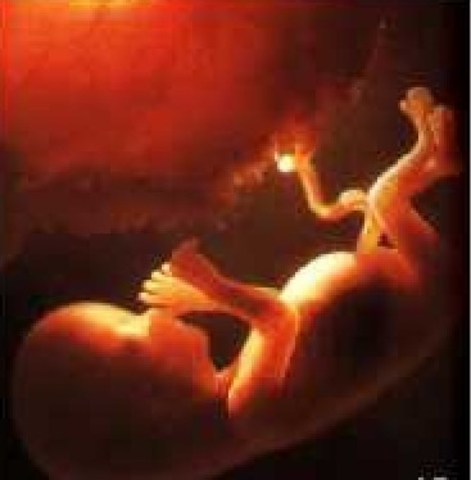

Period of the Fetus

Lasts from end of two months of pregnancy until birth.

• Month 4

Month 4

Baby is covered with thick, downy hair called lanugo. Mothers appetite increases and morning sickness is gone.